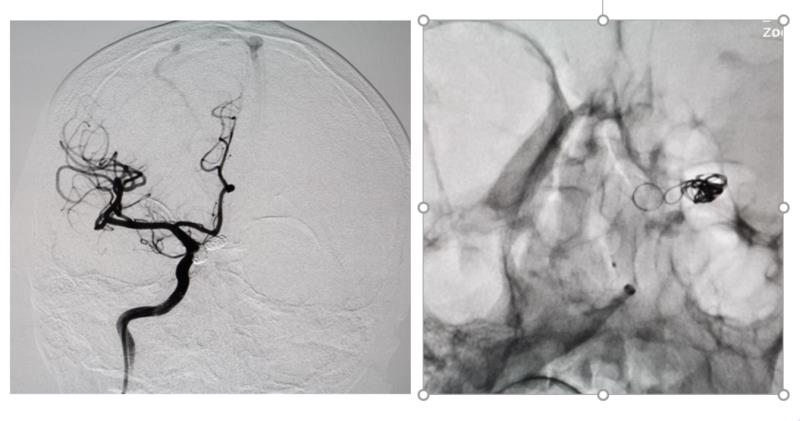

術后